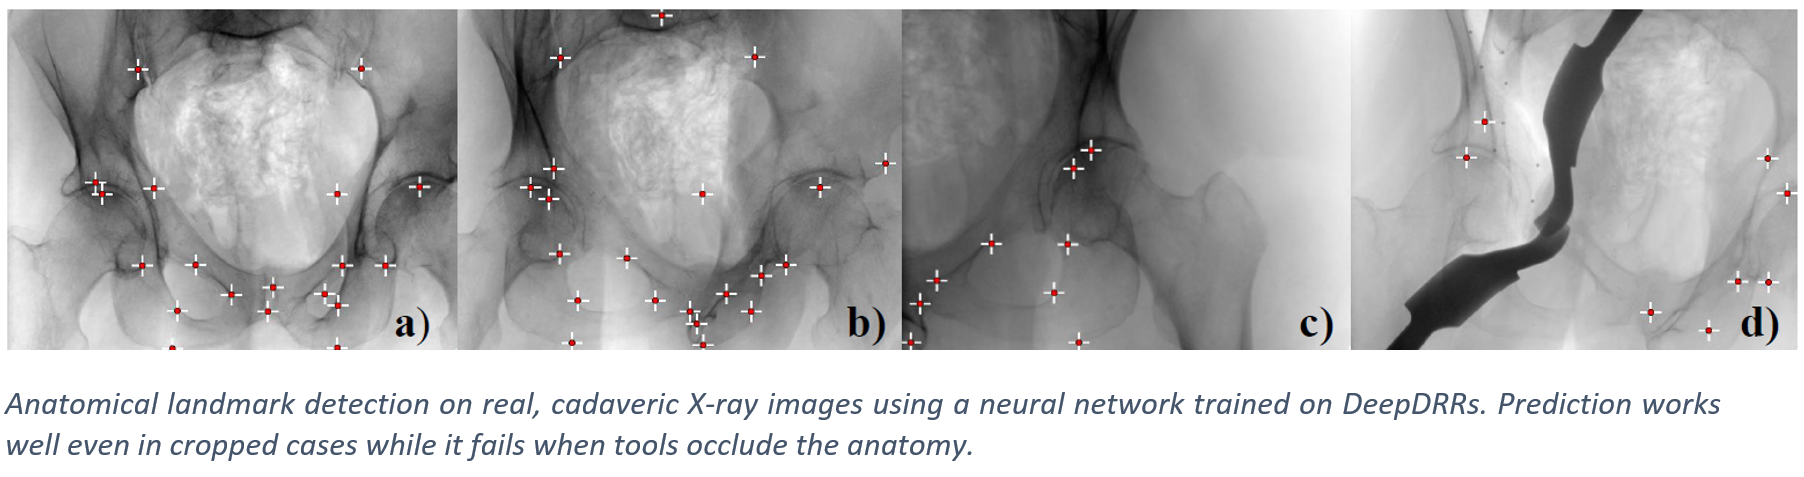

We have applied DeepDRR to anatomical landmark detection in pelvic X-ray: "X-ray-transform Invariant Anatomical Landmark Detection for Pelvic Trauma Surgery", also early-accepted at MICCAI'18: https://arxiv.org/abs/1803.08608 and now with quantitative evaluation in the IJCARS Special Issue on MICCAI'18: https://link.springer.com/article/10.1007/s11548-019-01975-5. The ConvNet for prediction was trained on DeepDRRs of 18 CT scans of the NIH Cancer Imaging Archive and then applied to ex vivo data acquired with a Siemens Cios Fusion C-arm machine equipped with a flat panel detector (Siemens Healthineers, Forchheim, Germany). Some representative results on the ex vivo data are shown below.